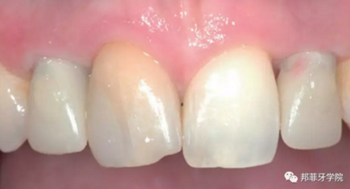

最終印模采用個性化印模柱,記錄穿齦輪廓(圖13)。CAD/CAM個性化基臺精確就位(圖14)。全瓷冠水門汀固位(圖15)。

6年后效果穩(wěn)定,患者滿意(圖16)。

圖 15-1:六個月后復(fù)查

圖 15-2:六個月后復(fù)查